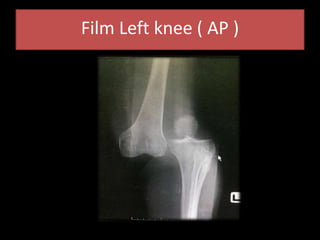

Film Left knee ( AP )

Differential diagnosis • FractureLeft patella • Fracture Left distal femur • Fracture Left proximal tibia • Left Knee dislocation • Ligament injury

Diagnosis • Posterolateral LeftKnee dislocation with R/O vascular injury • Mild head injury ( low risk ) • LW at Left upper eye lid